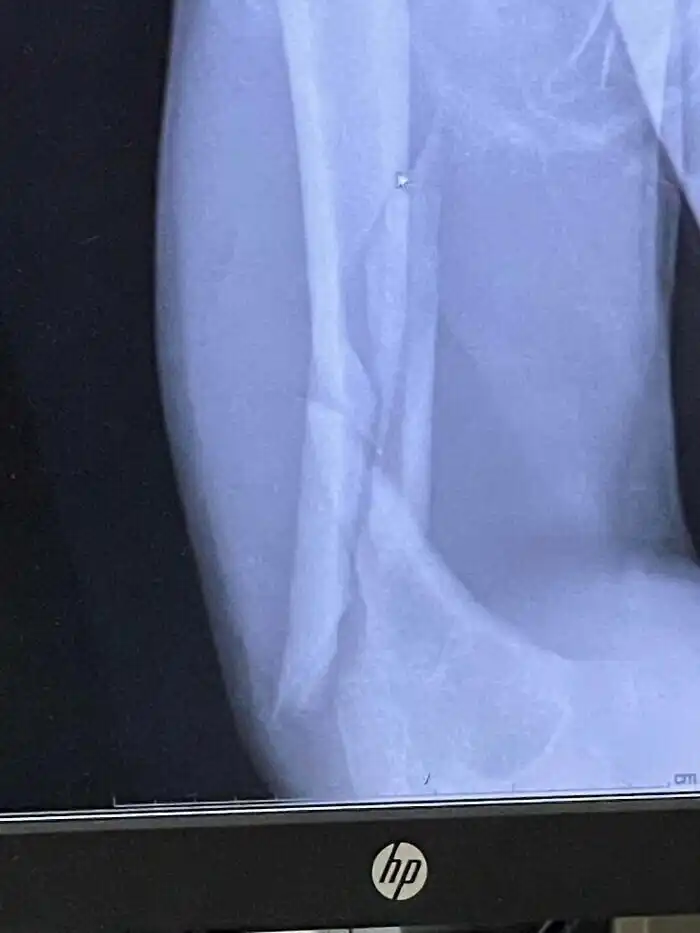

«Сломал и вывихнул руку. С днем рождения меня»